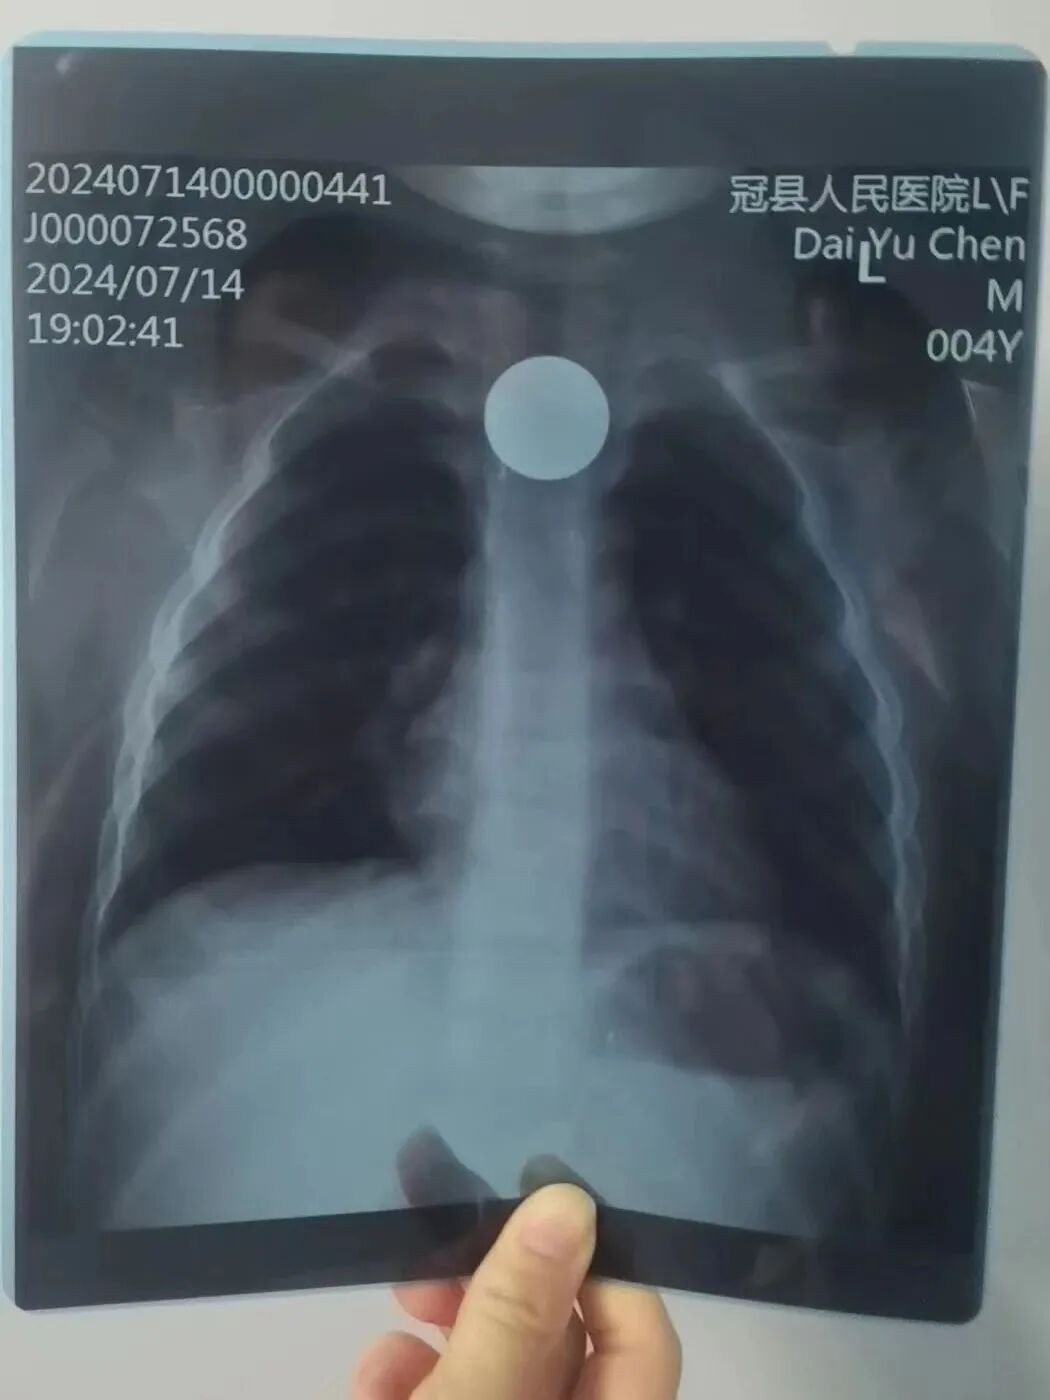

門診值班醫(yī)師接診了一名4歲孩童,據(jù)孩子母親告知,孩子在下午4點(diǎn)誤服了一枚一元的硬幣,進(jìn)行完相關(guān)檢查后已經(jīng)過(guò)去4個(gè)小時(shí),孩子咽部有明顯的不適感。根據(jù)孩子母親提供的癥狀,接診醫(yī)師立刻確診為食管內(nèi)異物,并迅速聯(lián)系消化內(nèi)鏡中心護(hù)士長(zhǎng)張利及聽(tīng)班醫(yī)生。消化內(nèi)鏡中心醫(yī)護(hù)人員用最短的時(shí)間到崗后立刻準(zhǔn)備操作物品,因孩子年齡小,禁食時(shí)間不夠,無(wú)法進(jìn)行無(wú)痛胃鏡下治療,與孩子母親溝通后立即安排普通胃鏡下行急診胃鏡下異物取出術(shù),內(nèi)鏡操作不到10分鐘,便成功將食管內(nèi)的一元硬幣取出。

圖片